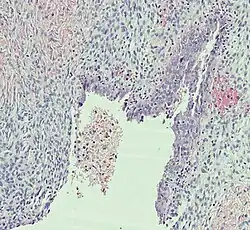

Histopathology

In case an ovarian cyst is surgically removed, a more definite diagnosis can be made by histopathology:

| Type | Subtype | Typical microscopy findings | Image |

| Functional cyst | Follicular cyst |

|

| Corpus luteum cyst |

| |